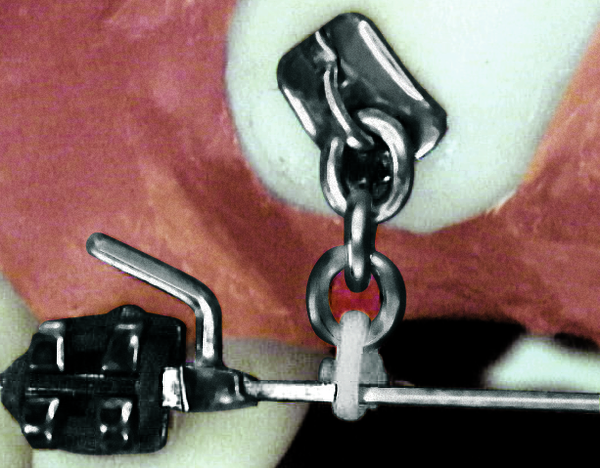

Kieferorthopädisches (KFO-) Implantat

Sollen Zähne in größerem Umfang verschoben werden, ist hier besonders bei Heranwachsenden häufig eine lange Behandlungsdauer notwendig, da ein suffizientes Widerlager zur Verankerung oft fehlt oder nicht ausreicht. In diesem Fall kann durch ein kieferorthopädisches (KFO-) Implantat (s.u.), als zusätzlichen Verankerungspunkt, ein schnellerer und oft einfacherer Behandlungsverlauf ermöglicht werden.

- kieferorthopädische Mini-Implantate (siehe Foto unten)

kieferorthopädisches (KFO-) Implantat